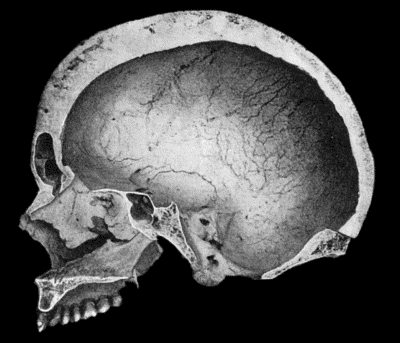

| 134. | Changes in the Skull resulting from Ostitis Deformans | 474 |

| 48. | Zanthoma of Hands | 188 |